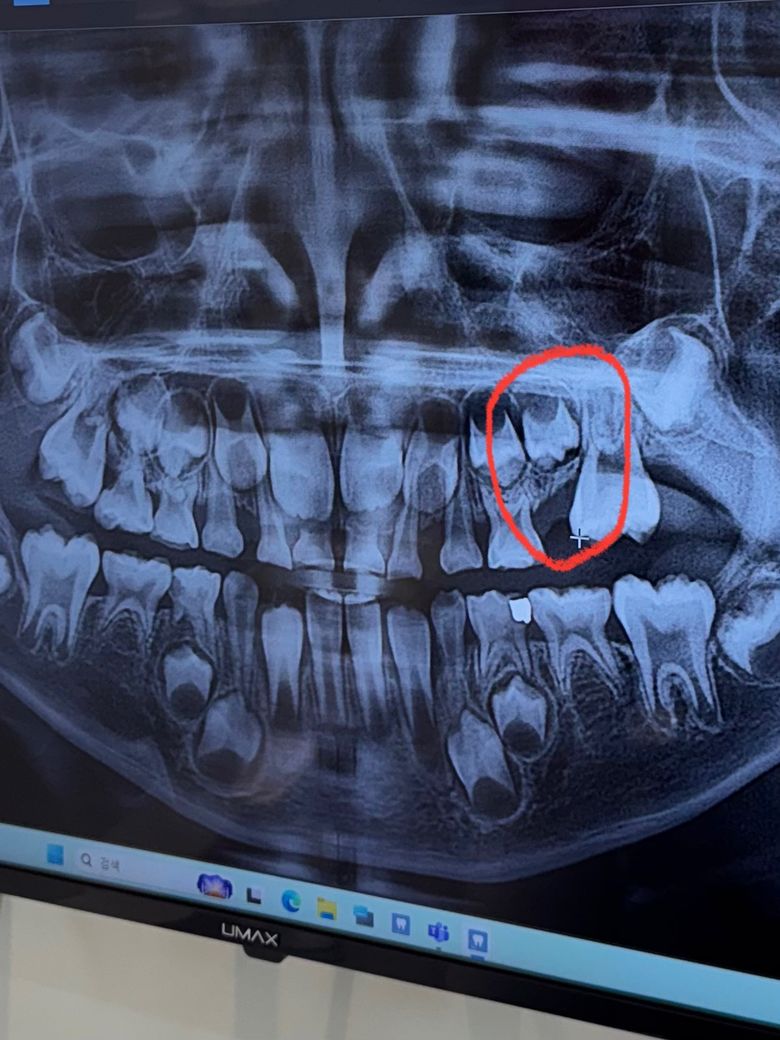

7살 아이 어금니가 빠져서 병원에 갔는데

공간유지 장치 여쭤봣더니 공간유지 장치를 걸 곳이 없어서 기다려야 할것 같다고 했었거든요

뒤에 나오는 어금니가 많이 자란거 같아서 오늘 다시 갓더니 송곳니( 아마도 영구치를 말씀하시는거 같아요)

송곳니가 없어서 공간이 괜찮을거 같다며

공간유지 장치 안해도 될것 같다고 하시거든요

저는 어금니 빠진곳 옆에 나오고있는 어금니가 빠진곳으로 기울어진거 같아서 더 자라면 빠진곳 매워질까봐 걱정인데 뭐가 나을까요?

지금 x-ray 에서 보아도 공간이 비좁아 간격 유지장치 하기가 어려울 것으로 보입니다. 그리고 왼쪽 윗송곳니가 파노라마 사진에서 보이지 않습니다. 선천적 결손인 것으로 보입니다.

#26 치아가 근심으로 많이 기울어진것으로 보입니다. 영구치아가 기울어져 맹출공간이 없어지게 되면 부정교합이 생길수있기때문에 공간관리가 필요합니다.

엑스레이 사진상 영구치 송곳니 치배가 없어서 결손은 맞는 것 같습니다. 다만, 그 문제와는 별개로 왼쪽 위 제2유구치(E)가 다소 빨리 빠져서 그 뒤 제1대구치(6번치아)가 기울어지고, 공간이 닫힐 염려가 있는 것은 맞습니다.

그래서 공간유지장치를 해주면 좋으나 보통 하는 distal shoe 유지장치의 경우 그 뒤 제1대구치가 온전히 맹출되어야 걸 수 있습니다. 아직 온전히 맹출하지 않은 치아에 대해서는 사용하지 못하고요. 완전 맹출했을 때 유지장치를 만들어 장착해줄 수도 있고, 아니면 그냥 두고 나중에 어금니 직립에 대한 교정을 해줄 수도 있습니다.